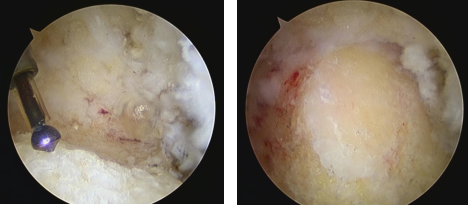

確定好手術(shù)方案后,石榮劍副院長(zhǎng)及曹廣超主任、趙亮主治醫(yī)師手術(shù)團(tuán)隊(duì)為患者進(jìn)行了關(guān)節(jié)鏡下手術(shù)。術(shù)中先在足跟后方內(nèi)外兩側(cè)做5mm切口,在關(guān)節(jié)鏡下檢查發(fā)現(xiàn)跟腱止點(diǎn)部分跟腱變性、局部鈣化,跟腱滑囊增生、水腫,Haglund畸形骨突明顯,鏡下徹底清理變性組織,切除增生骨突,置入錨釘固定跟腱末端。僅用時(shí)30分鐘,手術(shù)順利結(jié)束。

術(shù)中關(guān)節(jié)鏡下